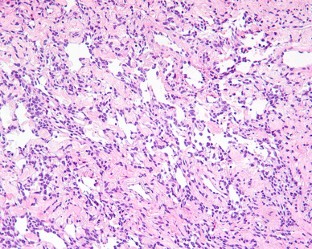

Solitary fibrous tumors (SFTs) are well recognized in the head and neck region, but rarely arise in the sinonasal tract (SNT). Six primary SNT SFTs were identified in the files of Southern California Permanente Medical Group between 2006 and 2017. The patients included five males and one female ranging in age from 33 to 72 years (mean 52 years), most of whom presented clinically with nasal obstruction. Three tumors involved the nasal cavity alone, one involved the paranasal sinuses, and two involved both the nasal cavity and paranasal sinuses. Histologically, the tumors were characterized by a variably cellular proliferation of cytologically bland spindle cells within a collagenous stroma with prominent interspersed branching vessels. Mitotic activity was low (range 0–2 per 10 high power fields) and there was no evidence of pleomorphism or tumor necrosis. Surface ulceration was noted. By immunohistochemistry, the lesional cells were positive for CD34, STAT6 and bcl-2. Clinical follow up information was available for all patients (range 32–102 months; mean 72 months). There were no recurrences or metastases and all were alive with no evidence of disease at last follow-up. SFTs rarely affect the SNT, but should be considered in the differential diagnosis of SNT mesenchymal lesions. Immunohistochemical expression of STAT6 can aid in diagnosis and separation of SFT from other spindle cell lesions occurring at this anatomic site. In combination with cases reported in the literature, primary SNT SFT behave in an indolent manner with conservative treatment.

Fig. 3